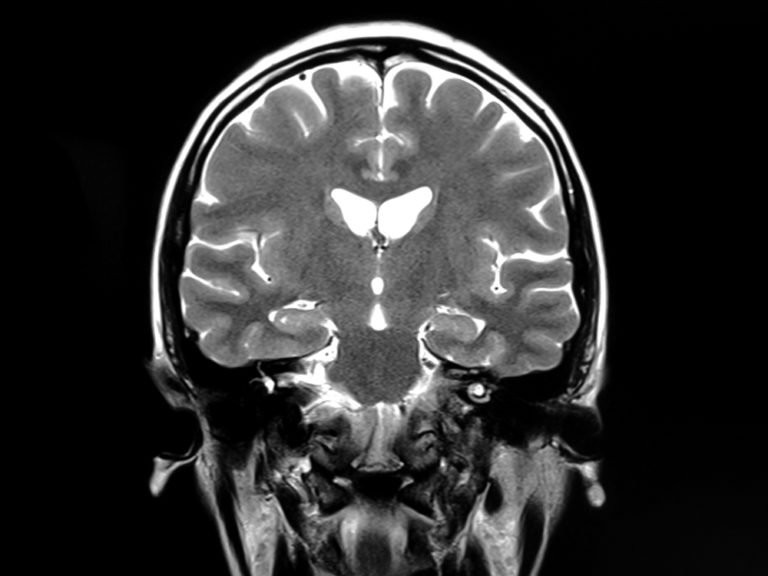

Subarachnoid hemorrhage

Hemorrhaging is terrible wherever it may occur, but it’s particularly bad when it happens in the space between the brain and its protective tissues. While shoulder pain is one possible symptom—as well as neck pain, vision problems, numbness, confusion, sensitivity to light, nausea, and seizures (among others)—the telltale sign of a subarachnoid hemorrhage (SAH) is a sudden and debilitating headache. This condition can be caused by a brain aneurysm, trauma, or blood thinners, and you’ll need immediate medical intervention to prevent brain damage and save your life. Here are 16 signs your headache could be something way worse.